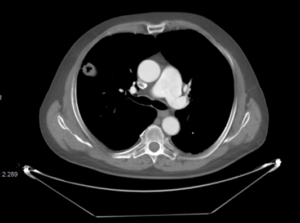

TC de tórax con contraste IV